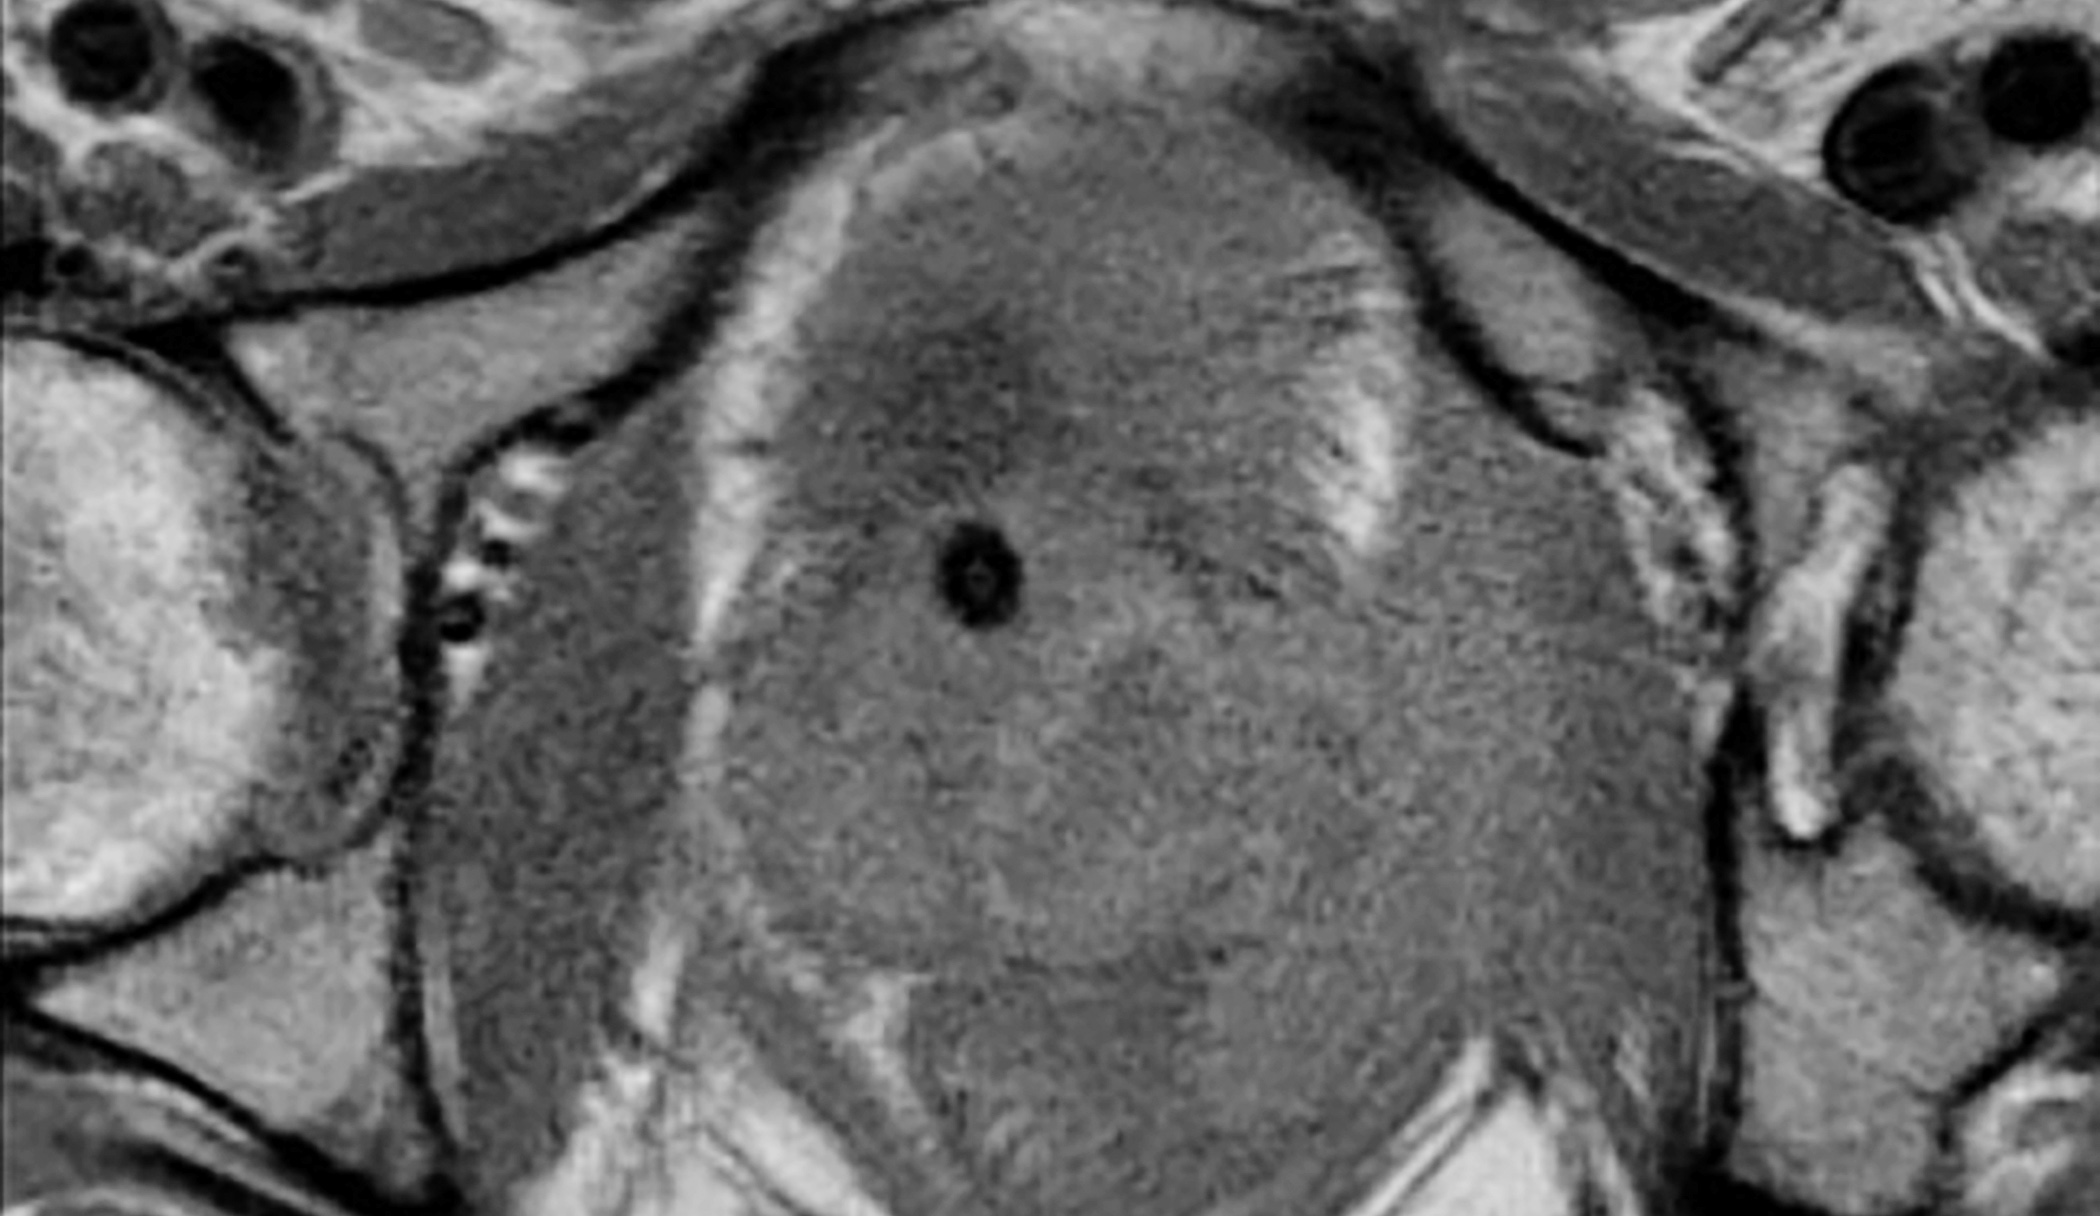

Abdominalschmerz – Prostataabszess

Bei Prostataabszessen handelt es sich um eine seltene Komplikation, die meist im Zusammenhang mit einer akuten oder chronischen Infektion des Organs oder der Harnwege auftritt. Neben dem Nachweis des Abszesses gilt es differenzialdiagnostisch entzündliche Prozesse der angrenzen Organe auszuschliessen. Hierbei können verschiedene bildgebende Verfahren zum Einsatz kommen.